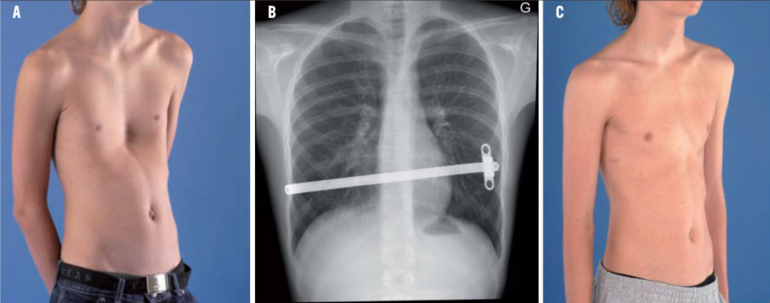

48+ Pectus Excavatum Chest Divot Images. For many people with pectus excavatum, the only sign or symptom is a slight indentation in their chests. If the condition is severe, it can look like the middle of the chest is scooped out, creating a deep hole.

Pectus excavatum, or funnel or sunken chest, occurs in both children and adults. If the condition is severe, it can look like the middle of the chest is scooped out, creating a deep hole. This can affect heart and lung function.

Pectus excavatum is a structural deformity of the anterior thoracic wall in which the sternum and rib cage are shaped abnormally. Its symptoms can affect people physically and psychologically. Pectus excavatum is a structural deformity of the anterior thoracic wall in which the sternum and rib cage are shaped abnormally. The breastbone and rib cage grow pectus excavatum is the main cause of rib flare.